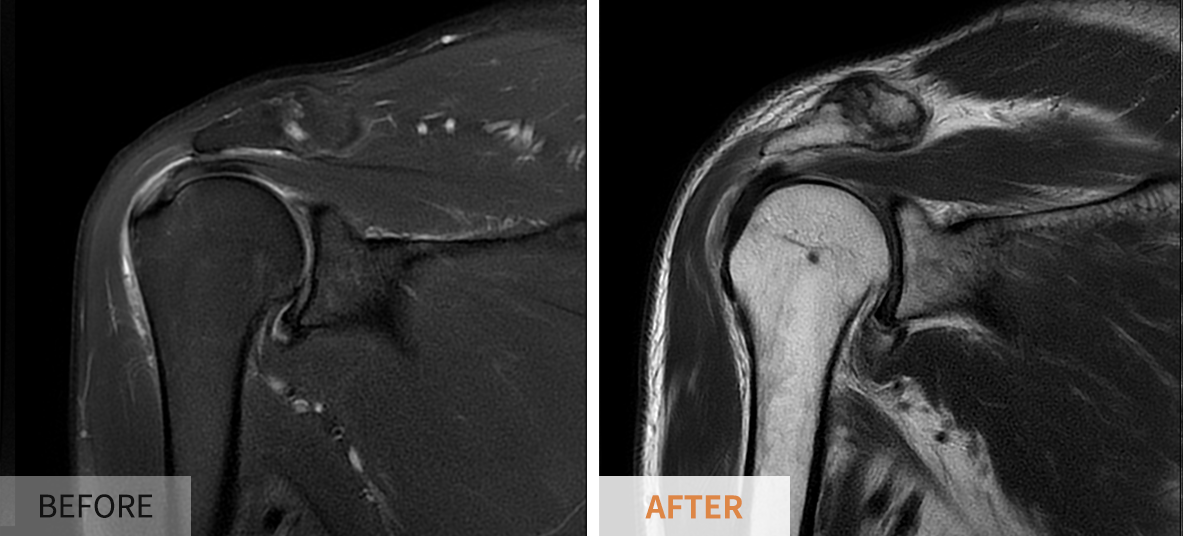

영상 검사

신체 검사 결과에 따라 추가적인 영상 검사가 필요할 수 있습니다. 일반적으로 사용되는 검사 방법에는 ▶️ X-레이, ▶️ 초음파, ▶️ MRI 등이 있습니다. X-레이는 뼈의 상태를 확인하는 데 도움을 주고, 초음파는 연조직의 구조와 상태를 파악하는 데 유용합니다. MRI는 보다 상세하게 손상의 정도를 평가할 수 있어 회전근개 파열 진단에서 특히 유용합니다.

수술적 치료

비수술적 치료에도 불구하고 증상이 계속될 경우, 수술적인 치료가 필요할 수 있습니다. 수술의 목적은 손상된 회전근개를 복구하고 어깨의 정상 기능을 회복하는 것입니다. 일반적으로, 이 과정은 내시경(subacromial decompression)을 통한 최소 침습 방법으로 진행됩니다. 수술 후에도 꾸준한 물리 치료와 재활 운동이 필수적입니다.